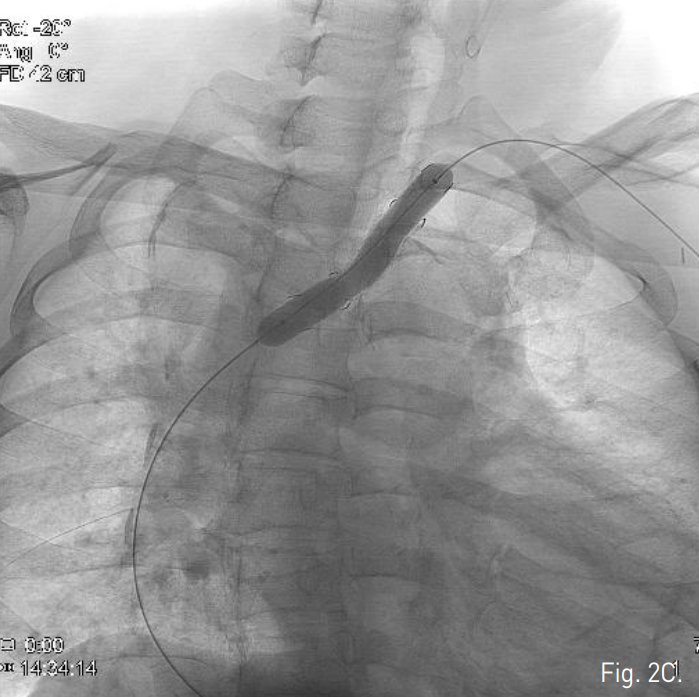

이후 12mm, 6cm 크기의 stent-graft(S&G Biotec, Korea)를 stent-graft내에 endoleak부위를 포함하여 설치한 후 balloon catheter(Foxcross, Abbott, USA)를 이용하여 stent-graft를 확장시킴 (Fig. 2C). 시술 직후 시행한 혈관조영술과 일주일 후에 시행한 CT angiogram에서 더 이상 type II endoleak은 보이지 않았음(Fig. 2D & 3).

Fig. 2

C. After 12mm, 6cm stent-graft was deployed, the balloon dilatation was done using a balloon catheter.

D. Follow-up subclavian arteriography shows no residual endoleak.

Fig. 3

Follow-up CT after 1 week showed complete regression of the endoleak from the aneurysmal sac involving the aberrant left subclavian artery.